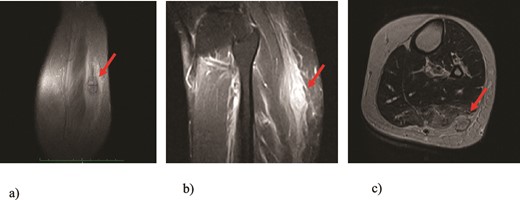

We present a case of a 49-year-old, female patient who presented at our clinic complaining of a growing painful mass with a diameter of ⁓3 cm in her left calf. The patient noticed the mass 2 months before the clinical exam and according to the anamnestic data it was growing progressively, becoming more painful, but only when touched, not spontaneously. She was first seen in another clinic, an ultrasound was performed and excision in local anesthesia was suggested. On presentation, clinical and ultrasound examinations were performed. Clinical exam revealed presence of a soft tissue mass on the medial side between the proximal and medial third of the left calf, of ⁓3 cm. It was placed deep in the subdermal area, mobile and not connected to the fascia. The ultrasound showed a heterogeneous, but predominantly hypoechoic mass with increased through transmission and increased vascularization (Fig. 1). Magnetic resonance imaging (MRI) was performed, confirming the presence of a soft tissue tumor in the subcutaneous tissue of the left calf (Fig. 2). Wide resection of the mass under spinal anesthesia was scheduled. Macroscopy of the specimen showed a whiteish soft fragment measuring 2 × 2 × 0.8 cm, microscopically composed of fibroblastic stroma with myxoid degeneration and immature osteoid embedded in between atypical osteoblasts with inconspicuous mitotic activity (Fig. 3). Foci of chondroid matrix with atypical chondrocytes were present. Necrotic and calcified bony trabeculae with osteoblastic rimming and adipose tissue with skeletal muscle were present on the periphery. The proliferative index, Ki67 was ⁓5%, thereupon a diagnosis of low-grade ESOS was made (Fig. 4). The regular staging follow-up was performed with chest and abdominal computed tomography (CT). No signs of metastatic disease were detected. The bone scan with Tc99m showed an increased uptake on the left iliac bone, highly suspected of Paget disease. Another surgery was scheduled. This time, re-resection procedure to achieve negative margins, as well as a biopsy of the iliac wing was performed. Negative margins were accomplished with the re-resection procedure. Grossly, the iliac bone biopsy was composed of five bony fragments measuring 0.5–1.5 cm. Microscopy showed sclerotic and irregularly shaped anastomosing, lamellar bony trabeculae with focal irregular calcification. The trabeculae contain osteocytes without atypia, rimmed with reactive osteoblasts, as well as multinucleated osteoclast giant cells. Granulation tissue with focal collagen deposition was present focally in between the bone trabeculae. Focal bone marrow was present. The microscopic analysis was consistent with the late (sclerotic) phase of Paget disease of bone (Fig. 5). On the last follow-up exam, 2 years after the surgery there is no evidence of local recurrence.

MRI findings of the tumor (arrows): (a) T1 image, coronal view; (b) T2 image, sagittal view; (c) T1 image, axial view revealing presence of a well-defined soft tissue tumor positioned in the subcutaneous fat tissue of the left calf with size of 3 cm and swelling of the surrounding muscles.